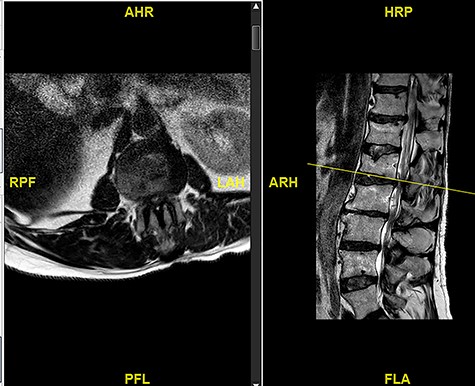

A 56-year-old male patient lumber decompression in a local neurosurgical centre for severe canal stenosis at L1/2 and L2/3 (Fig. 1) level after presenting with bilateral leg weakness and perianal numbness. Three months later he presented with recurrence of right leg pain radiating into the calf and worsening back pain as well as distal lower limbs weakness bilaterally with no sphincter problem. Following an magnetic resonance induction (MRI), which revealed a disc prolapse at L1/2 (Fig. 2), the patient was referred to our Centre. The images were reviewed by a consultant radiologist and as a possibly of intradural herniated disc disease was described. Intraoperatively no extradural disc prolapse was found, so midline durotomy was performed. Intradural disc herniation (IDH) was identified, which was communicating with the disc space through a midline defect in anterior dura (Fig. 3). This was removed extracted under the microscope. Post-operatively, he had a CSF leak needing re-suturing of dura. The patient did make a good post-operative recovery with no major sensory or motor deficits or sphincter disturbance.

MRI image revealing a recurrence of a disc prolapse, suspected to be an intradural disc at L1/2, confirmed intraoperatively.